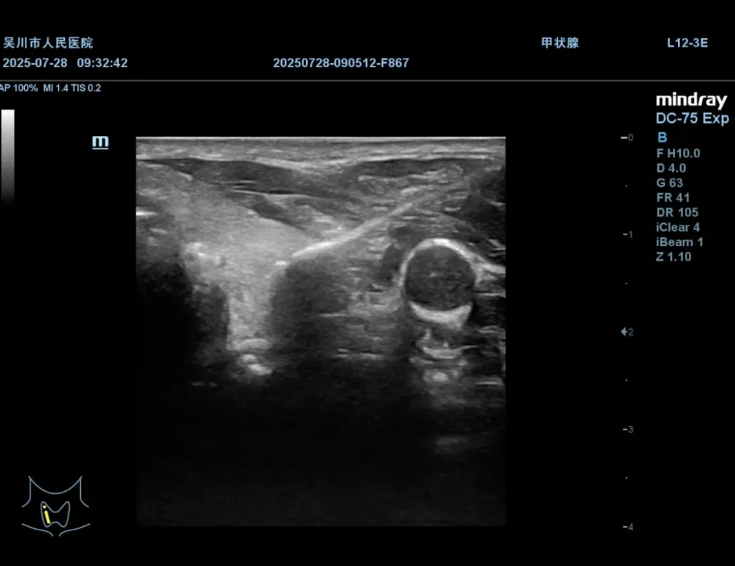

打好隔离带保护周围神经和血管

超声引导下消融针精准穿刺至结节内部

手术中,刘志对手术路径规划、消融范围把控等关键环节进行了细致指导,与我院超声科陈兴华医生默契配合,在实时超声引导下精准操作,将消融针直达病灶,通过能量释放使肿瘤组织凝固坏死,实现原位灭活。整个过程患者生命体征平稳,术后仅留下微小穿刺点,恢复速度也远超传统手术,极大地减轻了患者的痛苦,患者及家属对治疗效果十分满意。